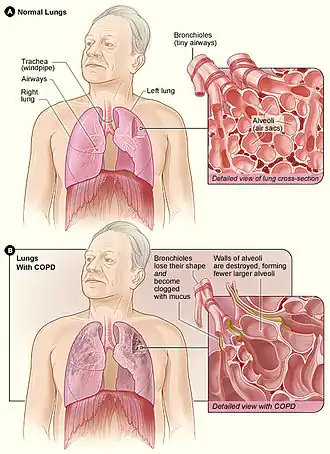

| Em cima: pulmões saudáveis com pormenor em corte dos bronquíolos e dos alvéolos pulmonares. Em baixo, as mesmas estruturas em processo de destruição pela DPOC | |

A doença pulmonar obstrutiva crónica (português europeu) ou crônica (português brasileiro) (DPOC) é um tipo de doença pulmonar obstrutiva caracterizada por diminuição prolongada do calibre das vias aéreas respiratórias e destruição do tecido pulmonar.[1] Entre os principais sintomas estão falta de ar e tosse com produção de expectoração. A DPOC é uma doença progressiva, o que significa que geralmente se agrava com o decorrer do tempo.[8] A partir de determinado momento começam-se a verificar dificuldades em realizar atividades do dia-a-dia, como subir escadas.[3] Bronquite crónica e enfisema são termos antigos usados para denominar diferentes tipos de DPOC.[3][9] O termo "bronquite crónica" é ainda hoje usado para definir uma tosse produtiva que se manifeste durante pelo menos três meses por ano e ao longo de dois anos.[10]

Fisiopatologia

A DPOC é um tipo de doença pulmonar obstrutiva caracterizada por uma limitação crónica e apenas parcialmente reversível das vias aéreas, verificando-se também a incapacidade de expirar por completo.[2] A limitação é o resultado da destruição do tecido pulmonar (denominada "enfisema") e de doença das pequenas vias aéreas (denominada "bronquiolite obstrutiva"). A contribuição de cada um destes fatores varia entre pessoas.[8] A destruição severa das pequenas vias respiratórias pode levar à formação de grandes bolhas de ar que substituem o tecido pulmonar. Esta forma da doença denomina-se "enfisema bolhoso".[60] Algumas pessoas com DPOC apresentam também algum grau de hiperresponsividade a irritantes semelhante ao que se verifica na asma.[18]

A DPOC tem origem numa resposta inflamatória significativa e crónica à inalação de irritantes.[8] Este estado inflamatório pode ainda ser agravado com infeções bacterianas crónicas.[58] Entre as células inflamatórias envolvidas estão os granulócitos neutrófilos e os macrófagos, dois tipos de leucócitos. Entre os fumadores estão também envolvidos os linfócitos T citotóxicos e algumas pessoas com DPOC apresentam envolvimento dos granulócitos eosinófilos de forma semelhante à asma. Parte desta resposta celular é provocada por mediadores inflamatórios, como os fatores quimiotáticos. Entre outros processos envolvidos na destruição do tecido pulmonar estão o stress oxidativo, provocado por concentrações elevadas de radicais livres no fumo do tabaco e libertados por células inflamatórias, e a destruição do tecido conjuntivo dos pulmões por proteases que não são suficientemente inibidas pelos inibidores da protease. A destruição do tecido conjuntivo dos pulmões é o que provoca o enfisema, o que por sua vez contribui para a restrição do fluxo de ar e, por último, para a má absorção e libertação de gases respiratórios. O desgaste generalizado dos músculos que muitas vezes se verifica na DPOC pode ser devido, em parte, aos mediadores inflamatórios libertados pelos pulmões no sangue.[8]

O estreitamento das vias aéreas deve-se à inflamação e cicatrização que nelas ocorre. Isto faz com que a pessoa seja incapaz de respirar na totalidade. A principal restrição no fluxo de ar verifica-se durante a expiração, uma vez que é nesta fase que a pressão no peito comprime as vias aéreas.[61] Isto pode fazer que permaneça nos pulmões o ar da respiração anterior quando se inspira novamente, o que aumenta o volume total de ar nos pulmões em qualquer dado momento. Este processo é denominado "hiperaeração" ou "hiperinsuflação pulmonar".[61][62] A hiperinsuflação por exercício físico está ligada à falta de ar na DPOC, uma vez que a respiração é menos confortável quando os pulmões estão já parcialmente cheios.[63] A hiperinsuflação pode também agravar-se durante uma exacerbação.[64]